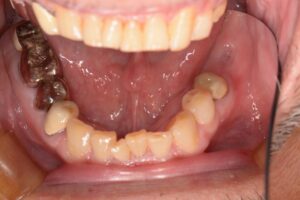

今回は奥歯を抜歯になってしまった患者様のケースです。

治療前の写真です。

この後、右下の奥歯も歯が割れてしまったことで抜歯になりました。